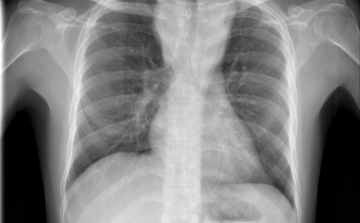

Egy líbiai menekülttáborból érkezhetett Európába a tbc egy új kórokozója

Menekültek révén, egy líbiai táborból érkezhetett Európába a tuberkulózis (tbc) kórokozójának egy korábban ismeretlen, gyógyszerekkel szemben ellenálló fajtája - írta a Die Welt című német lap a hírportálján szerdán.

Terjed a tbc Szatymazon?

Hétfő reggel óta tbc-tesztet végeznek el a gyerekeken egy szatymazi általános iskolában, ahol egy hete fertőző tüdőbetegségben halt meg egy korábban ott dolgozó nő - közölték az M1 aktuális csatorna déli Híradójában.

Csökkent a tbc-fertőzések száma Európában

Átlagosan 4,3 százalékkal csökkent az új tuberkulózisos (tbc-s) esetek száma 2010 és 2014 között az Egészségügyi Világszervezet (WHO) 53 országot magába foglaló európai régiójában.

Van miért aggódnunk

A tuberkulózis, a kanyaró, a HIV és a rezisztens baktériumok terjedése aggodalomra adhat okot Európában – állapították meg a régió járványügyi szervezetének (ECDC) éves jelentésében.

40 millió dohányos halhat meg tbc-ben 2050-ig

A kutatók szerint akár a 40 milliót is elérheti azoknak a dohányosoknak a száma, akik 2050-ig tuberkulózisban (tbc) veszítik életüket.